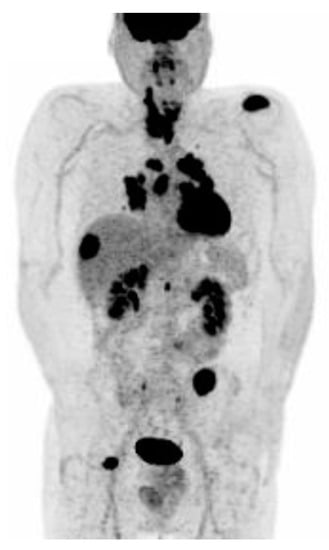

3.4.1. Radiodine Whole Body Scintigraphy

3.4.2. Positron Emission Tomography